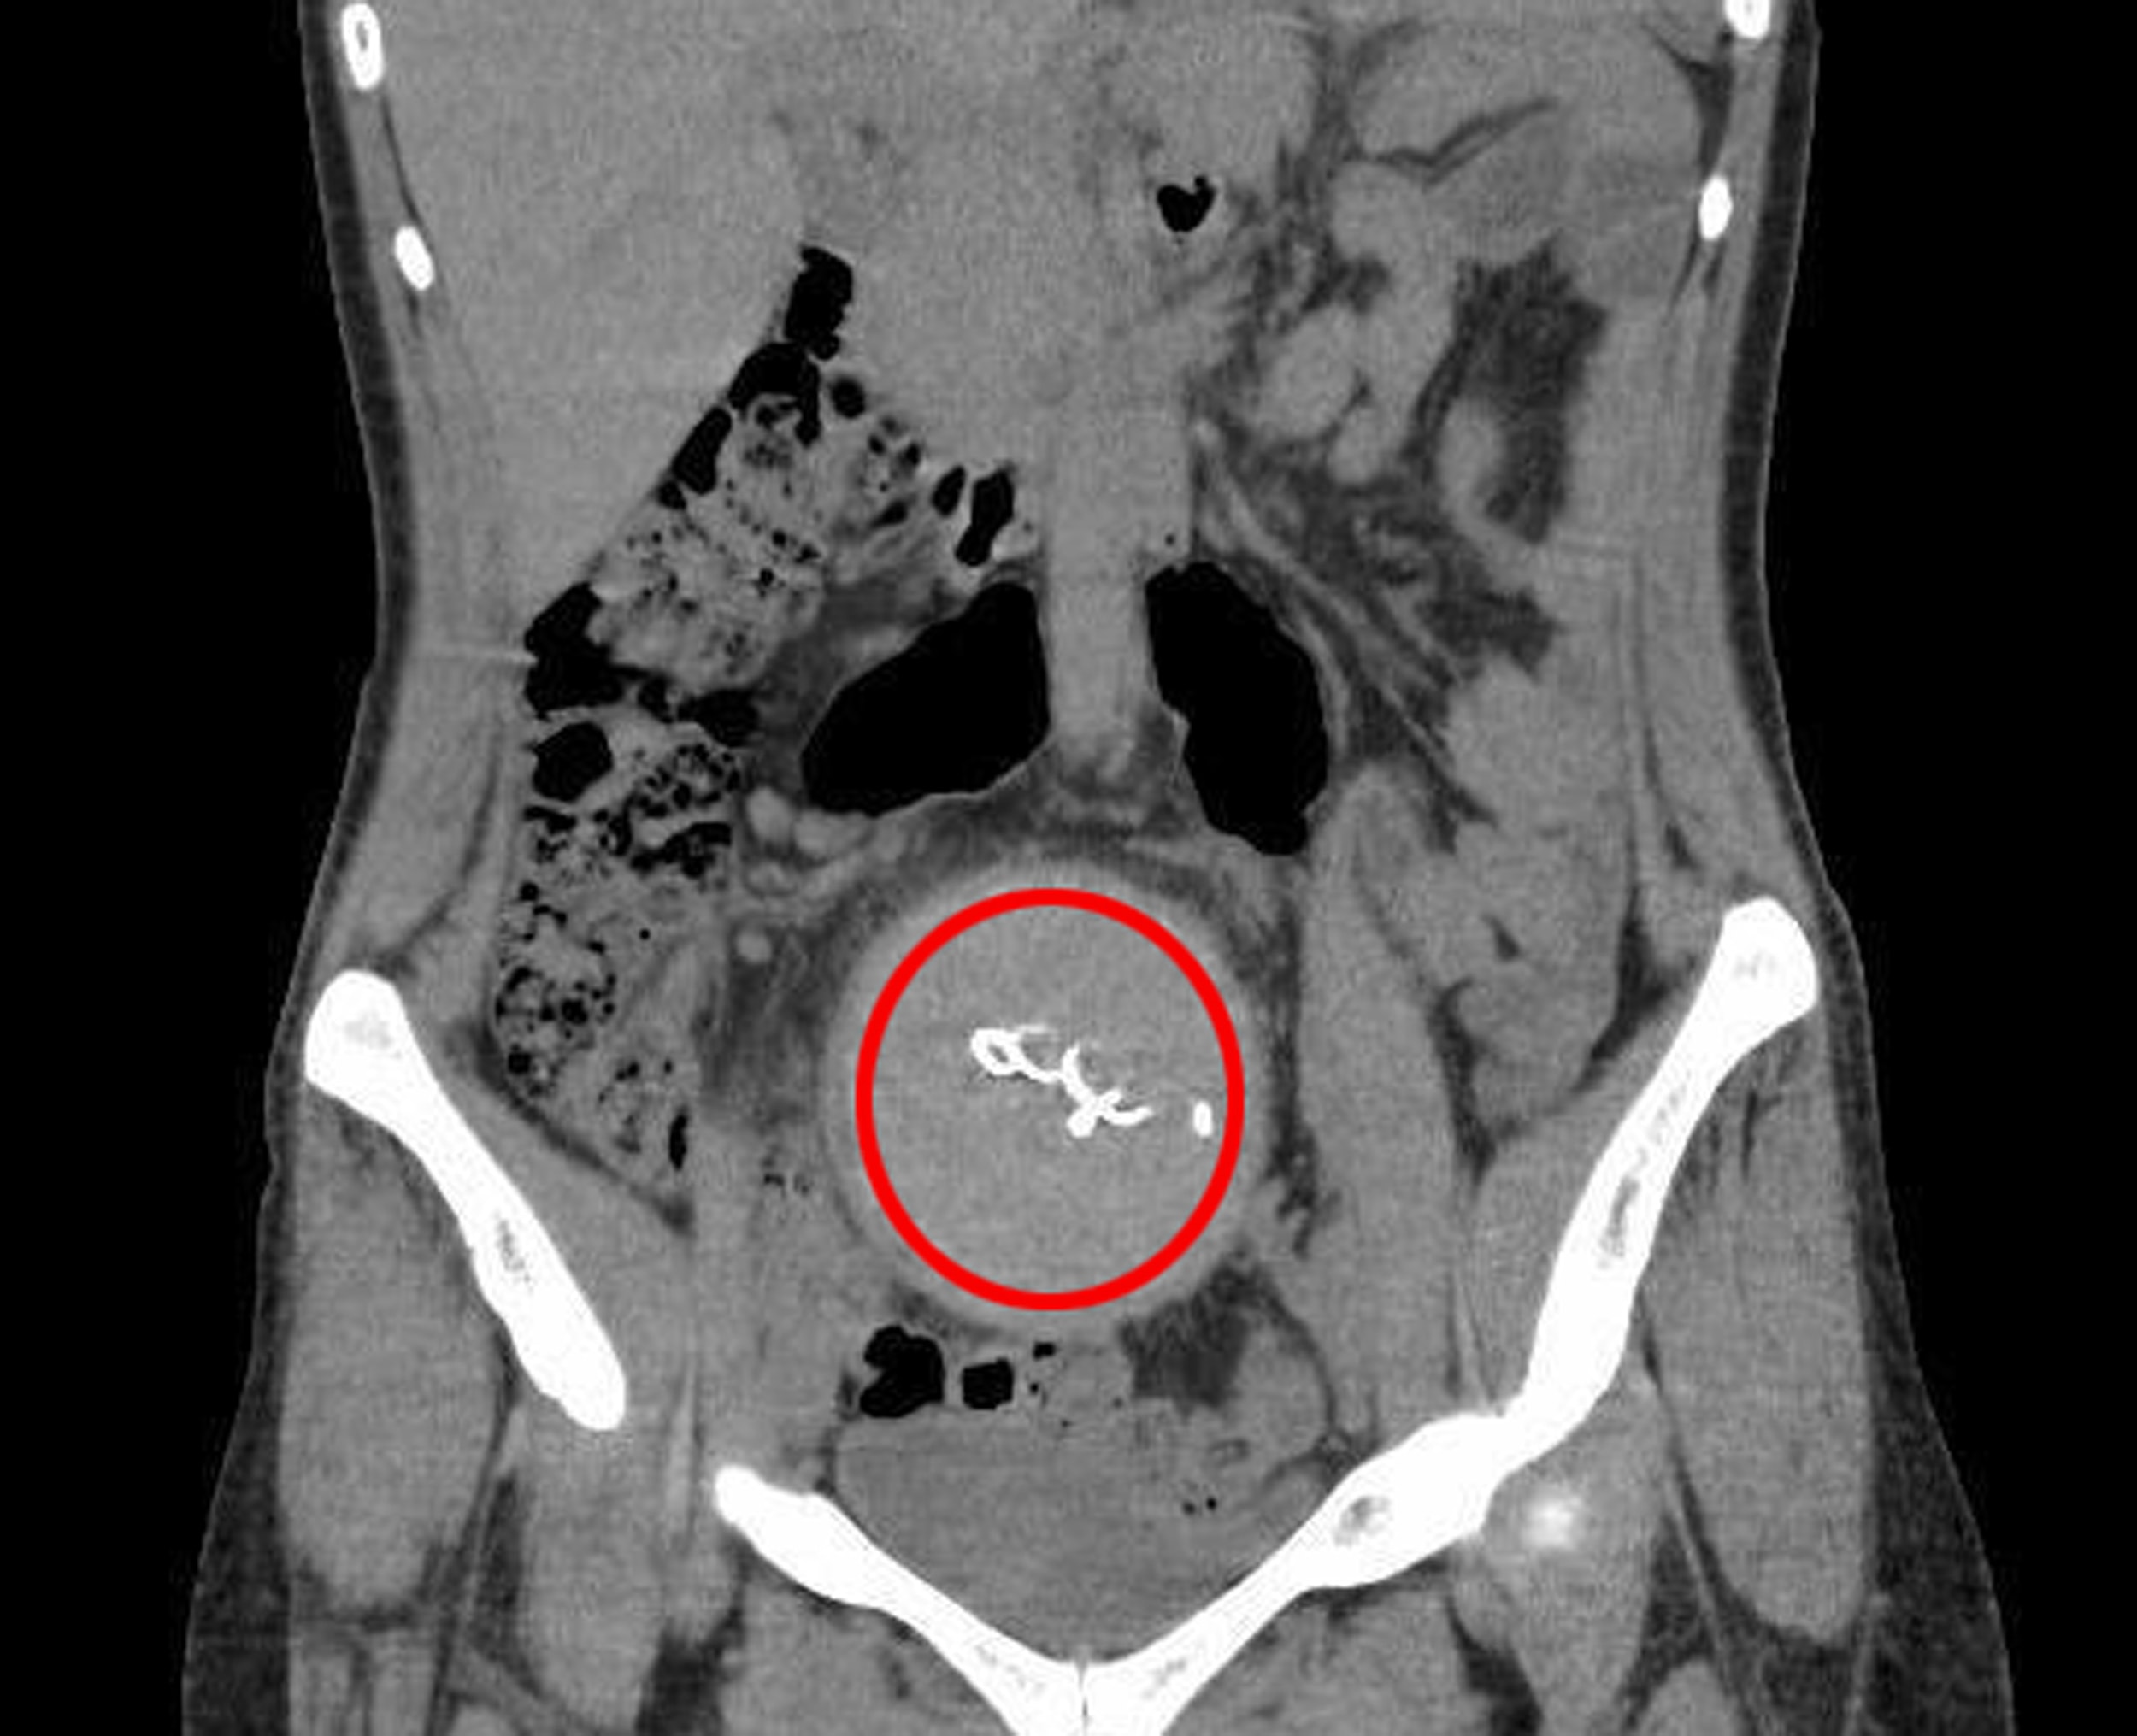

Burada yapılan kontrolde doktor acil tomografi çektirmesini istedi. Çekilen tomografide Y.S.nin vücudunda doğum sonrası unutulan sargı bezi görüldü. Büyük şok yaşayan Y.S., 2 yıldır yaşadığı ağrılara ihmalin sebep olduğunu öğrendi. Y.S.'nin karnında unutulan yaklaşık 30 santimetre uzunluğundaki gazlı bez ameliyatla çıkarıldı. Y.S., hastane ve doktor hakkında hukuki süreci başlatması için avukatı Hasret Başa başvurdu.

Çok zor günler yaşadığını belirten Y.S., 2 yıl boyunca ağrılarının ve ara ara iltihap akışının devam ettiğini söyledi. Y.S., Farklı hastanelere de başvurdum ancak kimse bir teşhis koyamadı. En son Antalya Eğitim ve Araştırma Hastanesine başvurdum. Burada bana doğum sırasında vücudumda sargı bezi kaldığı söylendi. İlk doğum yaptığımda 10 gün boyunca ağrılarım yüzünden çocuğumu kucağıma bile alamamıştım" diye konuştu.